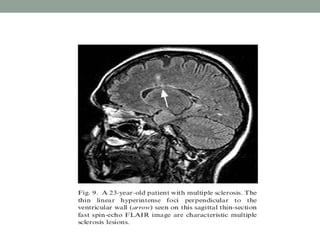

Fluid-attenuated inversion recovery

(FLAIR)

• T2-weighted imaging is well suited for lesion detection in

the brain because most lesions appear hyperintense with

this sequence.

• However CSF also appears hyperintense on T2-weighted

spin-echo (SE) images.

• Therefore, lesions at CSF interfaces, such as cortical sulci

and ventricles, may be mistaken for extensions of CSF or

partial volume effects.

• The conventional FLAIR technique employs a 180 degree

RF pulse to flip the net magnetization vector 180° and

null the signal from a particular entity (eg, water in tissue).

• When the RF pulse ceases, the spinning nuclei begin to

relax. When the net magnetization vector for water passes

the transverse plane (the null point for that tissue), the

conventional 90° pulse is applied, and the SE sequence

then continues as before.

• The interval between the 180° pulse and the 90° pulse is

the TI ( Inversion Time).

• FLAIR imaging suppresses signal from free water in CSF

and maintains hyperintense lesion contrast.

• FLAIR image have a long TR and TE and an inversion

time (TI) that is tailored to null the signal from CSF.

• FLAIR sequences are particularly useful in evaluation of

MS, infarcts, SAH